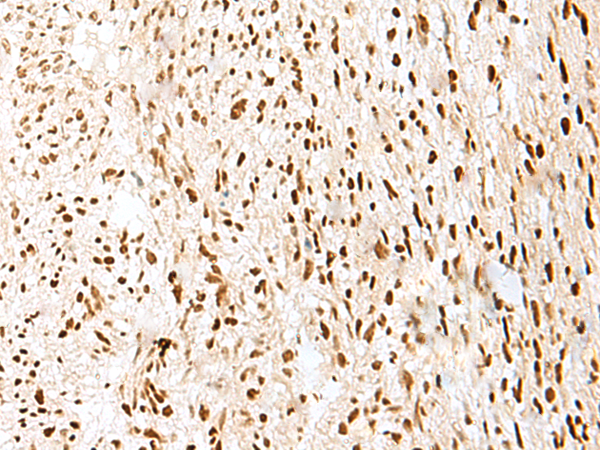

IHC positive control: |

Human cervical cancer and Human colorectal cancer |

IHC Recommend dilution: |

20-100 |